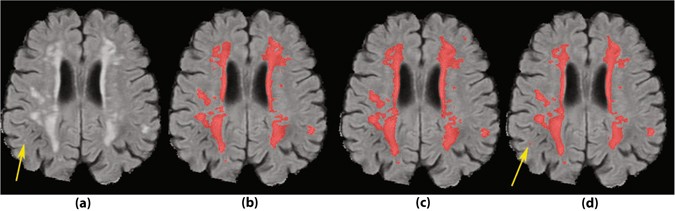

A sample case with a small lesion missed by the two human observers. (a) FLAIR image without annotations. (b) Segmentation by human observer 1. (c) Segmentation by human observer 2. (d) Segmentation by MSWS + Loc method.